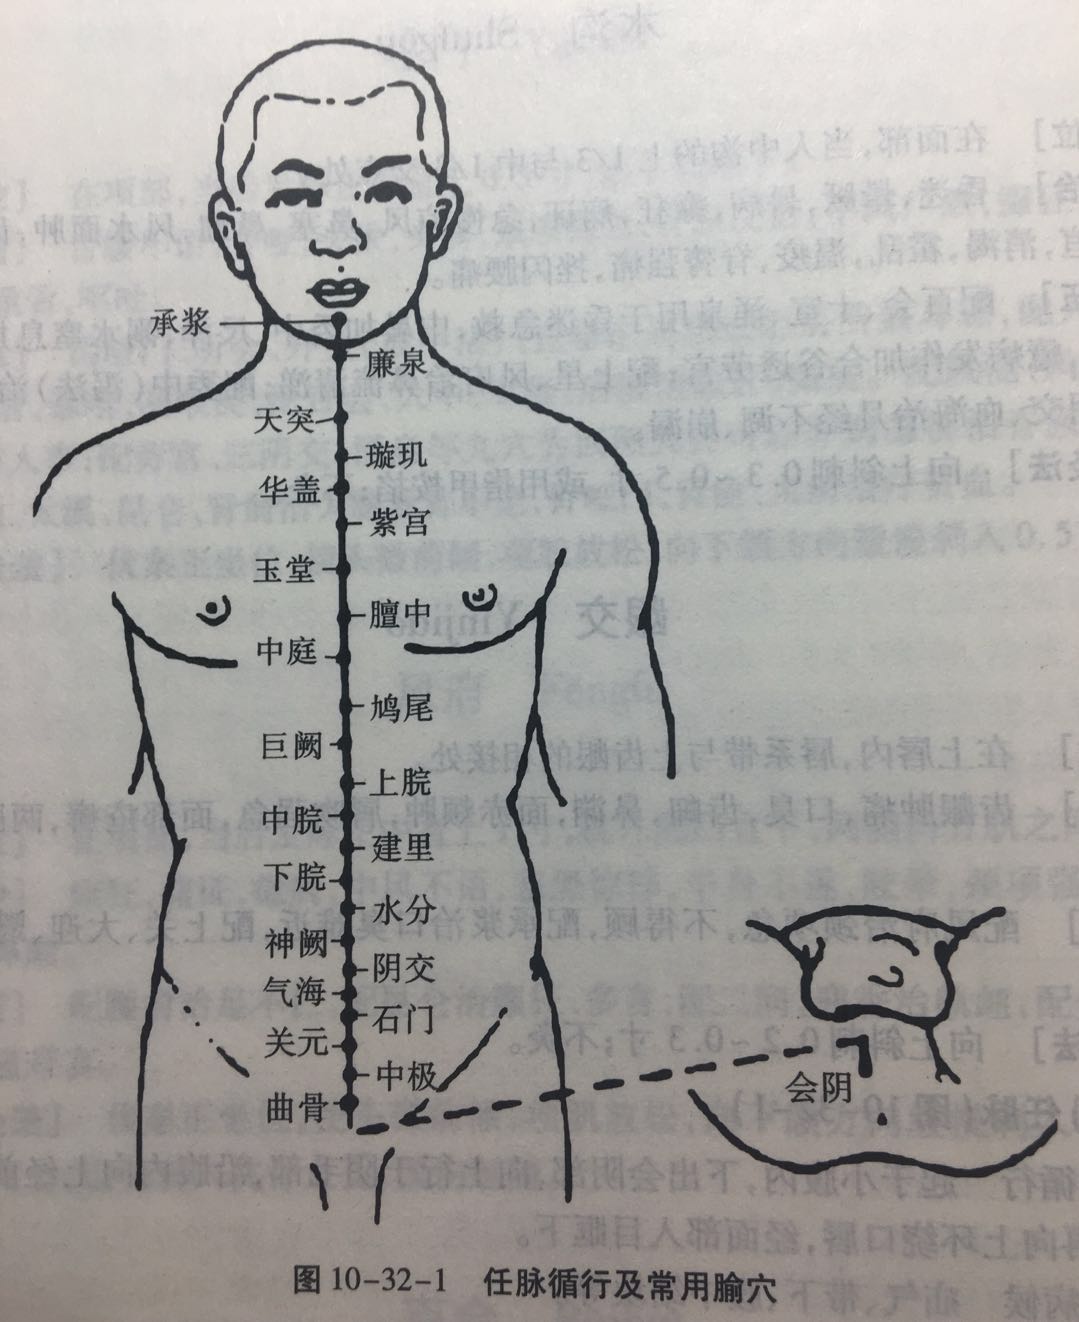

【(十四)任脉(图10-32-1)】

1、经脉循行 起于小腹内,下出会阴部,向上行于阴毛部,沿腹内向上经前正中线到达咽喉部,再向上环绕口唇,经面部入目眶下。

2、主要病候 疝气疝气、带下、腹中结块等。

3、主治概要 主治腹、胸、颈、头面的局部病证及相应的内脏器官疾病。少数腧穴有强壮作用或可治神志病。

4、督脉歌诀 任脉会阴两阴间,曲骨毛际陷中安,中极脐下四寸取,关元脐下三寸连,脐下二寸石门是,脐下寸半气海全,脐下一寸阴交穴,脐之中央即神阙,脐上一寸为水分,脐上二寸下脘列,脐上三寸名建里,脐上四寸中脘接,脐上五寸上脘在,脐上六寸巨阙穴,鸠尾蔽骨下五分,中庭膻下寸六取,膻中却在两乳间,膻上寸六玉堂主,膻上紫宫三寸二,膻上四八华盖举,膻上璇玑六寸四,玑上一寸天突取,廉泉颔下结上已,承浆颐前下唇中。

会阴

【定位】 在会阴部,男性当阴囊根部与肛门连线的中点,女性当大阴唇后联合与肛门连线的中点。

【主治】 溺水窒息,昏迷,癫狂,惊痫,小便难,遗尿,阴痛,阴痒,阴部汗湿,脱肛,阴挺,疝气,痔疾,遗精,月经不调。

【配伍】 配神门治癫狂痫,配水沟治溺水窒息,配十宣急救昏迷,配蠡(lí)沟治阴痒、阴痛(湿热下注型),配归来、百会治阴挺(中气下陷型),配承山治痔疮、脱肛,配支沟、上巨虚治便秘,配中极治遗尿、淋证,配关元治遗精。

【刺灸法】 直刺 0.5 ~ 1 寸,孕妇慎用;可灸。

中极

【定位】 在下腹部,前正中线上,当脐中下 4 寸。

【主治】 小便不利,遗尿不禁,阳痿,早泄,遗精,白浊,疝气偏坠,积聚疼痛,月经不调,阴痛,阴痒,痛经,带下,崩漏,阴挺,产后恶露不止,胞衣不下,水肿。

【配伍】 配大赫、肾俞、三阴交,次髎治阳痿、早泄、遗精、白浊、月经不调、痛经崩漏、产后恶露不止,胞衣不下、阴挺等证(肾气虚型),配阴谷、气海、肾俞治遗溺不止,配大敦、关元、三阴交治疝气偏坠,配水分、三焦俞、三阴交、气海、委阳治水肿,中极透曲骨配三阴交、地机治产后、术后尿潴留;中极透曲骨、配气海、膻中、足三里治尿潴留(老年人气虚)。

【刺灸法】 直刺 0.5 ~ 1 寸;可灸。孕妇慎用。

【附注】 足三阴、任脉之会。

关元

【定位】 在下腹部,前正中线上,当脐中下 3 寸。

【主治】 中风脱证,虚劳冷惫,羸瘦无力,少腹疼痛,霍乱吐泻,痢疾,脱肛,疝气,便血,溺血,小便不利,尿频,尿闭,遗精,白浊,阳痿,早泄,月经不调,经闭,经痛,赤白带下,阴挺,崩漏,阴门瘙痒,恶露不止,胞衣不下,消渴,眩晕。

【配伍】 配气海、肾俞(重灸)、神阙(隔盐灸)急救中风脱证,配足三里、脾俞、公孙、大肠俞治虚劳、里急、腹痛;配三阴交、血海、中极、阴交治月经不调(冲任不固,针用补法),配中极、大赫、肾俞、次髎、命门、三阴交治男子不育症、阳痿、遗精、早泄、尿频、尿闭、遗尿(肾阳虚衰、针补法或艾灸),配太溪、肾俞治泻痢不止、五更泄。

【刺灸法】 直刺 0.5 ~ 1 寸;可灸。孕妇慎用。

【附注】 足三阴、任脉之会。

气海

【定位】 在下腹部,前正中线上,当脐(qí)中下 1.5 寸。

【主治】 绕脐腹痛,水肿鼓胀,脘腹胀满,水谷不化,大便不通,泻痢不禁,癃淋,遗尿,遗精,阳痿,疝气,月经不调,痛经,经闭,崩漏,带下,阴挺,产后恶露不止,胞衣不下,脏气虚惫,形体羸瘦,四肢乏力。

【配伍】 配三阴交治白浊、遗精,配关元治产后恶露不止;配灸关元、膏肓、足三里治喘息短气(关元虚惫),配关元、命门(重灸)、神阙(隔盐灸)急救中风脱证,配足三里、脾俞、胃俞、天枢、上巨虚治胃腹胀痛、呃逆、呕吐、水谷不化、大便不通、泻痢不止(脾气虚弱),配足三里、合谷、百会治胃下垂、子宫下垂、脱肛。

【刺灸法】 直刺 0.5 ~ 1 寸;可灸。孕妇慎用。

【附注】 肓(huāng)之原穴。

神阙

【定位】 在腹中部,脐中央。

【主治】 中风虚脱,四肢厥冷,尸厥,风痫,形惫体乏,绕脐腹痛,水肿鼓胀,脱肛,泻痢,便秘,小便不禁,五淋,妇女不孕。

【配伍】 配三阴交治五淋,配公孙、水分、天枢、足三里治泻痢便秘、绕脐腹痛(脾肾不和),配长强、气海、关元治脱肛、小便不禁、肾虚、不孕症,神阙(隔盐灸)配关元、气海(重灸)治中风脱证。

【刺灸法】 禁刺;可灸。

中脘

【定位】 在上腹部,前正中线上,当脐中上 4 寸。

【主治】 胃脘痛,腹胀,呕吐,呃逆,反胃,吞酸,纳呆,食不化,疳积,鼓胀,黄疸,肠鸣,泄利,便秘,便血,胁下坚痛,虚劳吐血,哮喘,头痛,失眠,惊悸,怔忡,脏躁,癫狂,痫证,尸厥,惊风,产后血晕。

【配伍】 配百会、足三里、神门治失眠、脏躁,配膻中、天突、丰隆治哮喘,配梁丘、下巨虚治急性胃肠炎,配肝俞、太冲、三阴交、公孙治疗胃十二指肠球部溃疡,配上脘、梁门(电针 20 分钟)治胆道蛔虫症,配阳池、胞门、子户(针灸并用)治腰痛、痛经、月经不调(子宫不正);配气海、足三里、内关、百会治胃下垂。

【刺灸法】 直刺 0.5 ~ 1 寸;可灸。

【附注】 胃的募穴,八会穴之腑会,手太阳、少阳、足阳明、任脉之会。

膻(dàn)中

【定位】 在胸部,当前正中线上,平第 4 肋间,两乳头连线的中点。

【主治】 咳嗽,气喘,咯(kǎ)唾脓血,胸痹心痛,心悸,心烦,产妇少乳,噎(yē)嗝(gé),鼓胀。

【配伍】 配曲池、合谷(泻法)治急性乳腺炎,配内关、三阴交、巨阙、心平、足三里治冠心病急性心肌梗死,配中脘、气海治呕吐反胃,配天突治哮喘,配乳根、合谷、三阴交、少泽、灸膻中治产后缺乳,配肺俞、丰隆、内关治咳嗽痰喘,配厥阴俞、内关治心悸、心烦、心痛。

【刺灸法】 平刺 0.3 ~ 0.5 寸;可灸。

【附注】 心包之募穴,八会穴之气会。